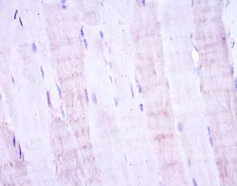

MAP2K4 Mouse Monoclonal antibody[5H4B4]

This gene encodes a dual specificity protein kinase that belongs to the Ser/Thr protein kinase family. This kinase is a direct activator of MAP kinases in response to various environmental stresses or mitogenic stimuli. It has been shown to activate MAPK8/JNK1, MAPK9/JNK2, and MAPK14/p38, but not MAPK1/ERK2 or MAPK3/ERK3. This kinase is phosphorylated, and thus activated by MAP3K1/MEKK. The knockout studies in mice suggested the roles of this kinase in mediating survival signal in T cell development, as well as in the organogenesis of liver.Tissue specificity: Abundant expression is seen in the skeletal muscle. It is also widely expressed in other tissues .

IHC    1/200 - 1/1000